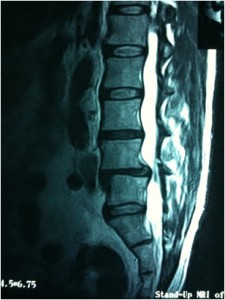

Pre-operative x-rays demonstrated a Grade I degenerative spondylolisthesis with instability on flexion-extension radiographs (Figures 1, 2). MRI findings (Figure 3) revealed disc bulging and uncovering of the intervertebral disc in addition to spondylolisthesis.

Figure 3. Lateral MRI demonstrates spondylolisthesis at L4-L5